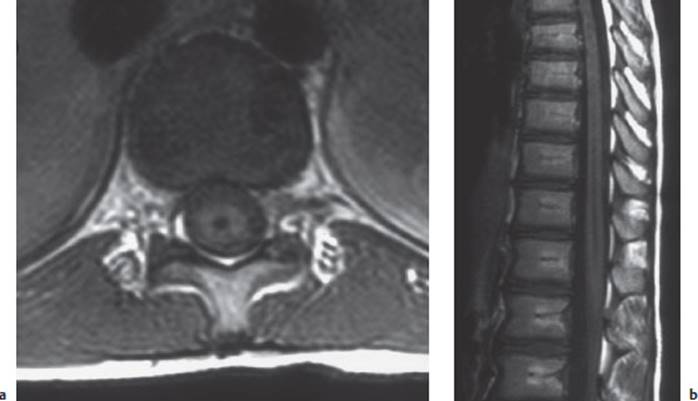

Diagnostic evaluation. Syringomyelia can be diagnosed from its typical symptoms and physical findings; the characteristic picture is of a dissociated sensory deficit combined with trophic disturbances. The diagnosis must then be confirmed with neuroimaging, specifically MRI (Fig.7.12).

Fig. 7.12 Thoracic syringomyelia (MRI). a The axial image reveals the expanded central canal as a cavity (syrinx) in the middle of the spinal cord. b The sagittal image shows the syrinx extending from T4 to the lower border of T8.